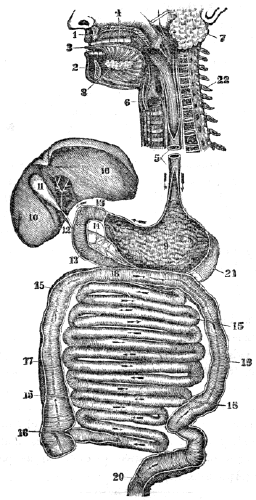

| 13. | Anatomy of the Digestive Organs, | 113 |

| 14. | Physiology of the Digestive Organs, | 124 |